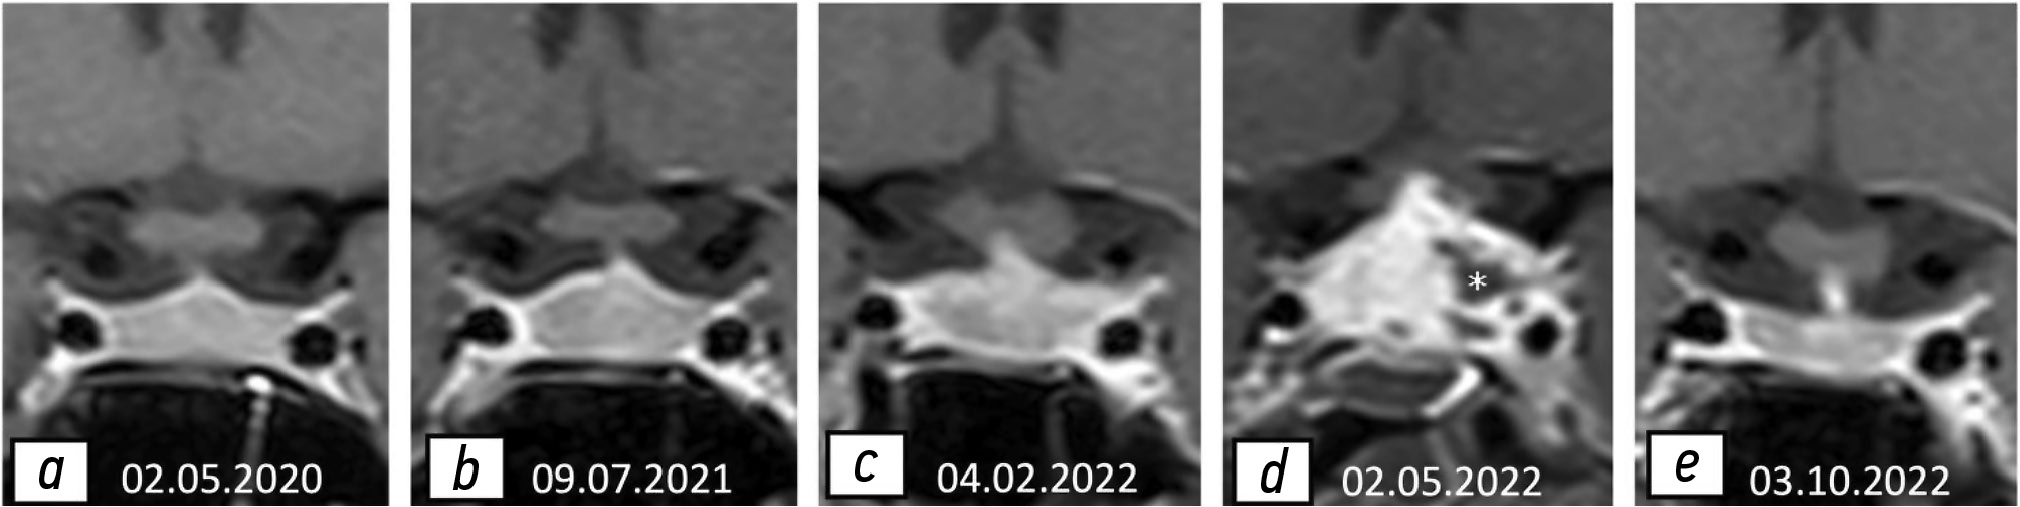

В мае 2022 г. у пациентки возник эпизод тяжёлой артериальной гипотензии (80/50 мм рт. ст.). С диагнозом недостаточности коры надпочечников пациентку госпитализировали в отделение эндокринологии. Результаты исследования содержания гормонов указывали на наличие признаков гипотиреоза и недостаточности коры надпочечников. Кроме того, при проведении МРТ головного мозга отмечено выраженное увеличение гипофиза и усиление гетерогенности его структуры (рис. 4).

Рис. 4. Результаты магнитно-резонансной томографии гипофиза, 02.05.2022: a — T1-взвешенное изображение в сагиттальной проекции; b — T2-взвешенное изображение в коронарной проекции; с — T1-взвешенное изображение в сагиттальной проекции с контрастированием. Отмечено резкое увеличение гипофиза, в основном за счёт супраселлярного компонента, структура неоднородна, контуры неровные. Хиазма сдавлена. Выявлено выраженное неравномерное утолщение слизистой оболочки клиновидной пазухи (звёздочки) в виде усиления интенсивности сигнала на T2-взвешенном изображении (b).

На этом этапе пациентка получала преднизон (утром и вечером — 10 и 5 мг соответственно) и каберголин (0,25 мг два раза в неделю). На фоне лечения состояние пациентки улучшилось. При проведении контрольной МРТ 03.10.2022 выявлено выраженное уменьшение гипофиза и снижение гетерогенности его структуры (рис. 5).

У пациентки выявлена тенденция к усилению, а в дальнейшем к ослаблению клинических и радиологических симптомов (рис. 6), что сопровождалось соответствующими изменениями содержания гормонов в сыворотке крови. На фоне применения глюкокортикостероидов её состояние улучшилось. Тем не менее после выписки из инфекционного стационара терапию глюкокортикостероидами, назначенную по поводу COVID-19, прекратили, что привело к резкому ухудшению состояния. Таким образом, лечение COVID-19 может влиять на течение других заболеваний, в частности АГ.

Рис. 6. T1-взвешенные изображения гипофиза в коронарной проекции с контрастированием: a — нормальные размеры и слегка гетерогенная структура; b, c — постепенное увеличение гипофиза в течение 21 месяца; d — выраженное увеличение гипофиза в течение трёх месяцев, наличие неконтрастной области, вероятно, вследствие некроза (звёздочка); e — гипофиз не увеличен, отмечена положительная динамика.